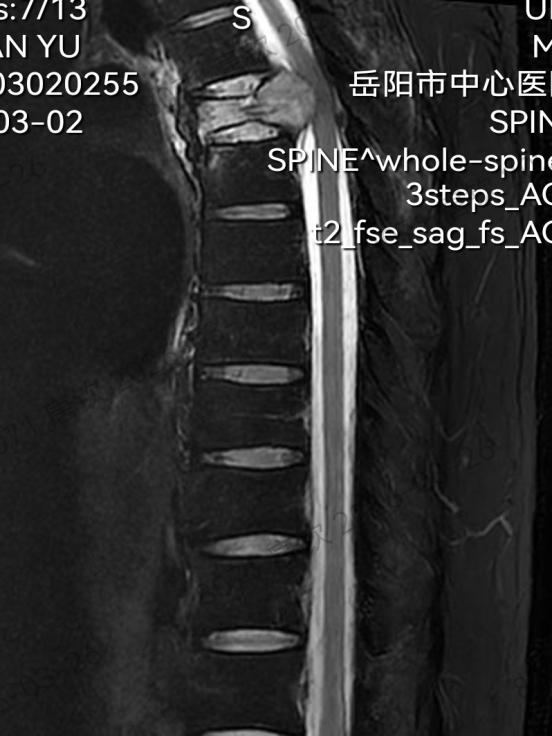

患者刘先生(化名)因顽固性胸背疼痛、渐进性呼吸困难,伴随双下肢进行性瘫痪入院,经详细检查确诊为第5胸椎侵袭性肿瘤。病灶位置极为特殊:椎体后方紧贴中枢脊髓,前方毗邻心脏、胸主动脉、气管、食管等关键脏器,解剖层次错综复杂、手术操作空间极度狭小,堪称外科手术的“雷区”。

术前影像检查图像